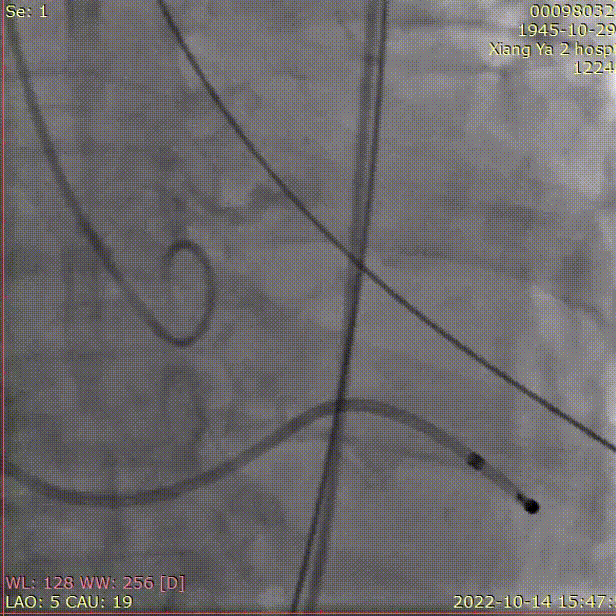

A.预扩张,并同时行主动脉造影

B. 冠脉保护:导丝、球囊、Guidezilla、位于LAD;Guiding回撤至升主动脉适当位置

C. 应用交界贴合技术调整人工瓣膜,标准位释放瓣膜并行释放后造影

D. 瓣膜释放后造影显示瓣膜位置良好

E.后扩张

F. 最终造影显示瓣膜位置良好冠脉开口血流正常,撤出冠脉保护

术后即刻评估

术后即刻TEE示主动脉瓣膜最大峰值血流速为2.4m/s,平均跨瓣压差为11mmHg,支架内未见明显反流或瓣周漏。